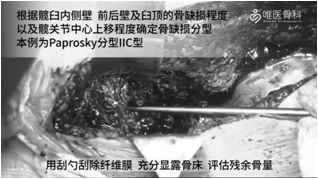

取出髋臼假体:去除髋臼周围的瘢痕组织,显露整个髋臼缘,取出已松动的全聚乙烯臼杯。然后用刮勺刮除纤维膜,充分显露骨床,评估残余骨量。根据髋臼内侧壁、前后壁及臼顶的骨缺损程度以及髋关节中心上移程度确定骨缺损分型。本病例髋臼骨缺损分型为:Paprosky ⅡC型。